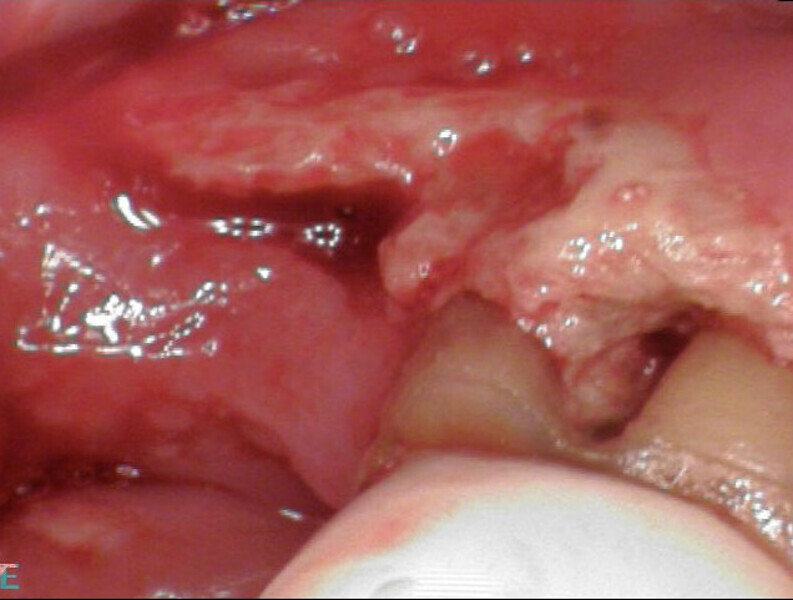

Our recommendations were a loading dose of antibiotics for ten days, followed by retreatment of the molar and antibiotics for five days. Unfortunately, her primary dentist ended up extracting the molar, the socket never healed and osteonecrosis of the jaw was established (Fig. 9). At this point, our recommendation was to have her treating doctor discuss treatment of this area with a maxillofacial specialist.

Figs. 9a & b: Osteonecrosis after extraction of the mandibular first molar.

Fig. 9b